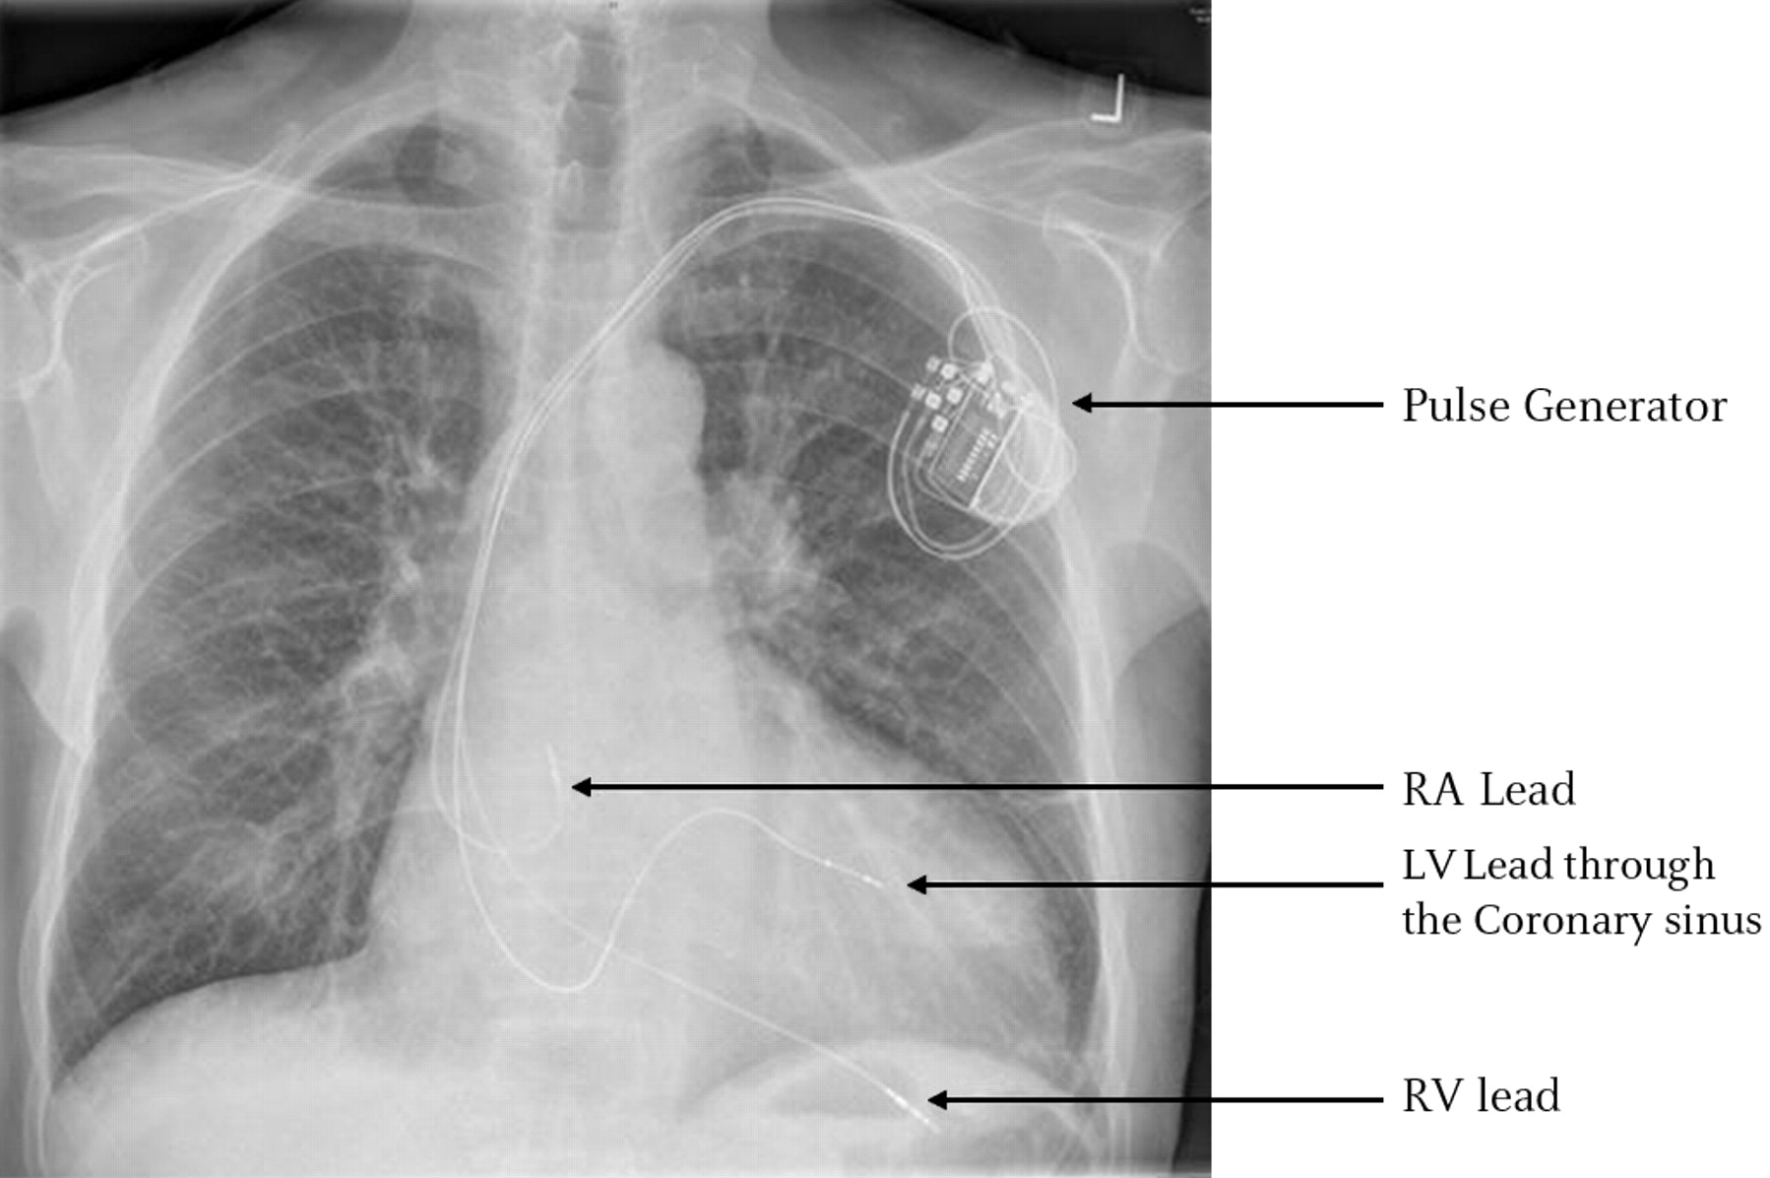

cxr rounds 2